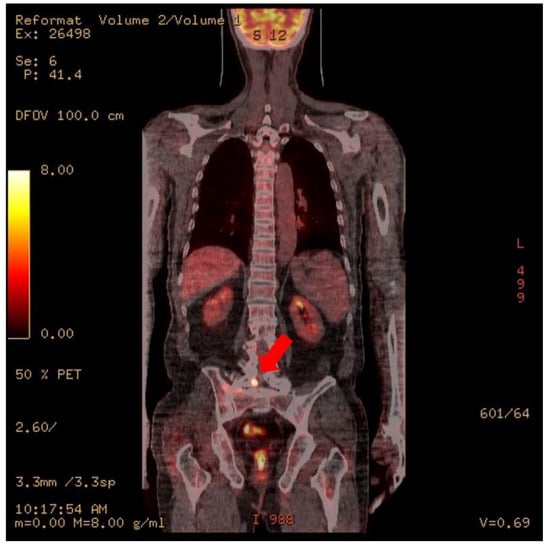

At the time of admission to the Hematology Oncology Department, an MRI of the lumbar spine showed suspicious findings of multifocal bone metastasis in the thoracic-lumbar spine, including T11-L5 and bilateral sacrum, iliac bones and epidural metastasis at L4/5, L5/S1 and the sacrum (Figure 1). PET-CT was also performed after the third R-CHOP at the time of admission to the Department of Hematology and Oncology, and showed residual hypermetabolic lesions in L5, the sacrum, and the right presacral area (Figure 2). Electrodiagnostic examination was performed five months after the onset (Table 1).

Figure 2. PET CT. Focal increased uptake is noted at right L5, the sacrum, and the presacral area (arrows).